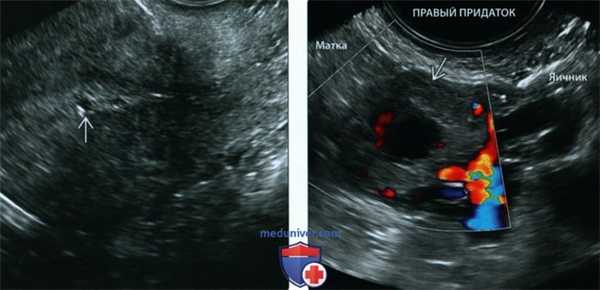

(Справа) При ТВУЗИ у той же пациентки в области придатка выявляется кольцо, представляющее собой плодное яйцо в маточной трубе, прилежащее к яичнику (курсоры). При ЦДК (рисунок не приводится) определялся усиленный кровоток («пылающее кольцо»), СГ- срок гестации. (Слева) При ТВУЗИ при осмотре объемного образования в области придатка визуализируются хорошо развитый эмбрион (курсоры) с окружающим его амнионом, расположенные внутри внематочного плодного яйца. Для описания данного случая подходит термин «установленная ВМБ».

(Справа) Данное изображение, сделанное при ТВУЗИ, демонстрирует значимость использования ЦДК в качестве вспомогательного средства при оценке области придатков. Визуализация кровотока вокруг кольца в области придатка позволяет легче отделить его от прилежащих петель кишечника. СГ - срок гестации. (Слева) При ТАУЗИ видно гомогенное объемное образование - гиперэхогенный сгусток в позадиматочном пространстве В Кистозная структура справа представляет собой желтое тело. Матка пустая. Эта картина может быть описана как возможная ВМБ. Гетерогенное объемное образование - самая частая ультразвуковая находка при трубной беременности.